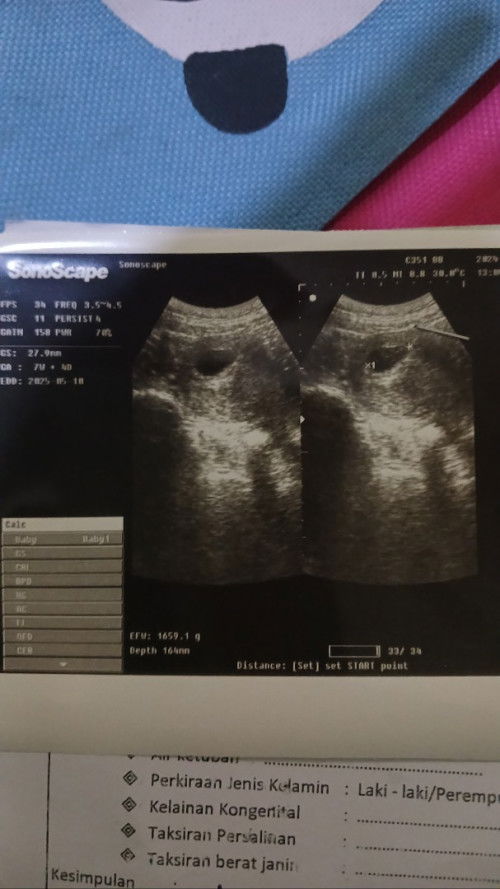

Bunda...Hpht saya tgl 18 Juli 2024 Hari ini saya habis usg dari hasil usg terhitung 7 minggu 4 hari. Tp pas pertama pemeriksaan bidan bilang udh terhitung 9 minggu. Ada yg sama ga bund hitungan'y ga sama